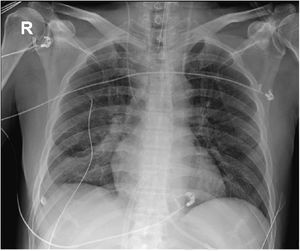

La intervención se realizó de manera programada en quirófano bajo control radiológico y ecocardiográfico (figs. 2 y 3).